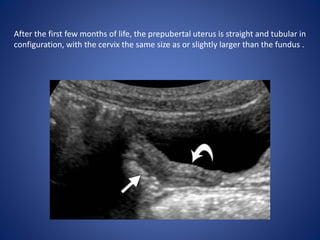

After the first few months of life, the prepubertal uterus is straight and tubular in

configuration, with the cervix the same size as or slightly larger than the fundus .

• 57.

After the firstfew months of life, the prepubertal uterus is straight and tubular in configuration, with the cervix the same size as or slightly larger than the fundus .